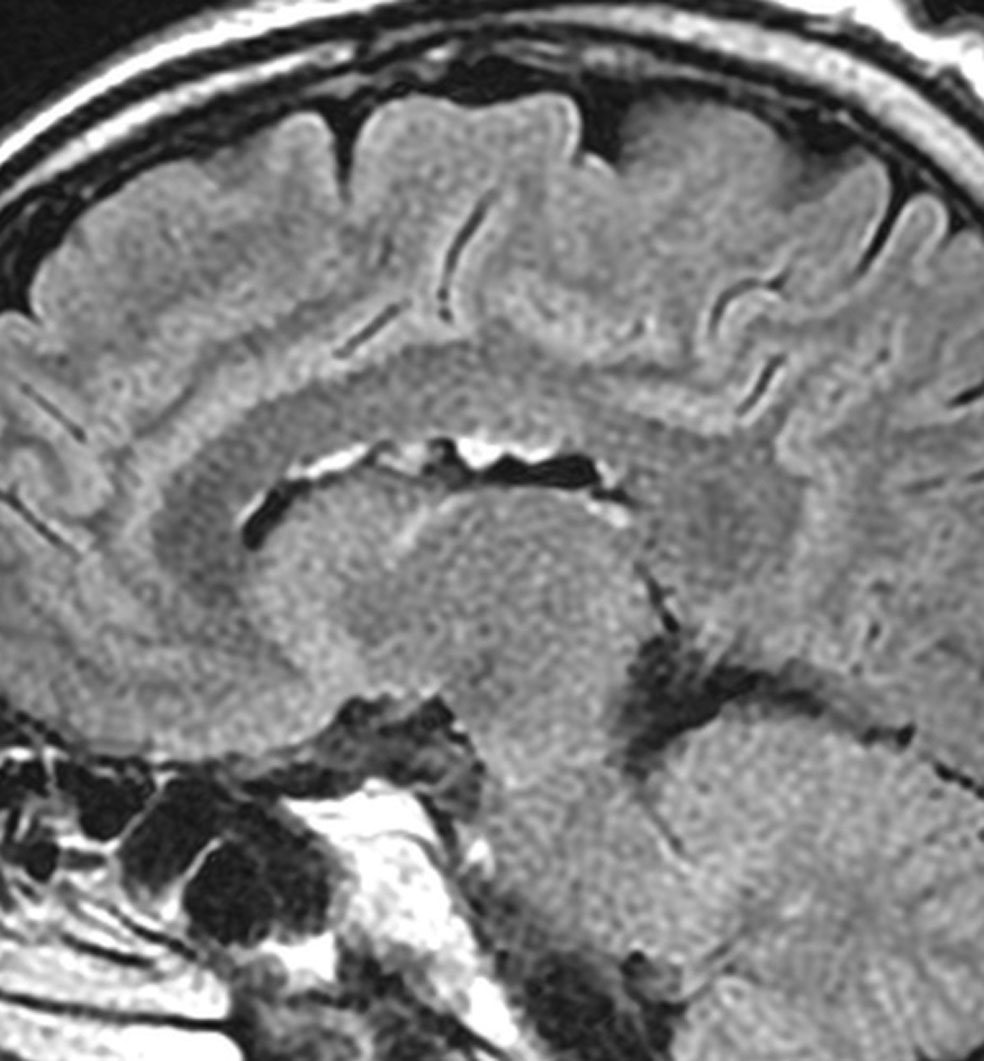

無症状で偶然発見された47歳女性の側脳室内上衣下腫

無症候で偶然発見された左側脳室前角尾状核頭に接したsubependymoma。定位脳生検で病理診断を得たましたが,3年間の観察で徐々に増大しました。左上が発見時,1年後(右上),2年後(左下),3年後(右下)

CTではやや低吸収,T1ガドリニウムでは低信号となりガドリニウム増強されません。小さな上衣下腫の場合は等吸収あるいは等信号のものも多いです。小さく点状に造影されている部分があるがこれは定位脳手術痕(track)です。

左中前頭回からの経皮室法 left middle frontal gyrus transcortical approach で全摘出できました(右図)。